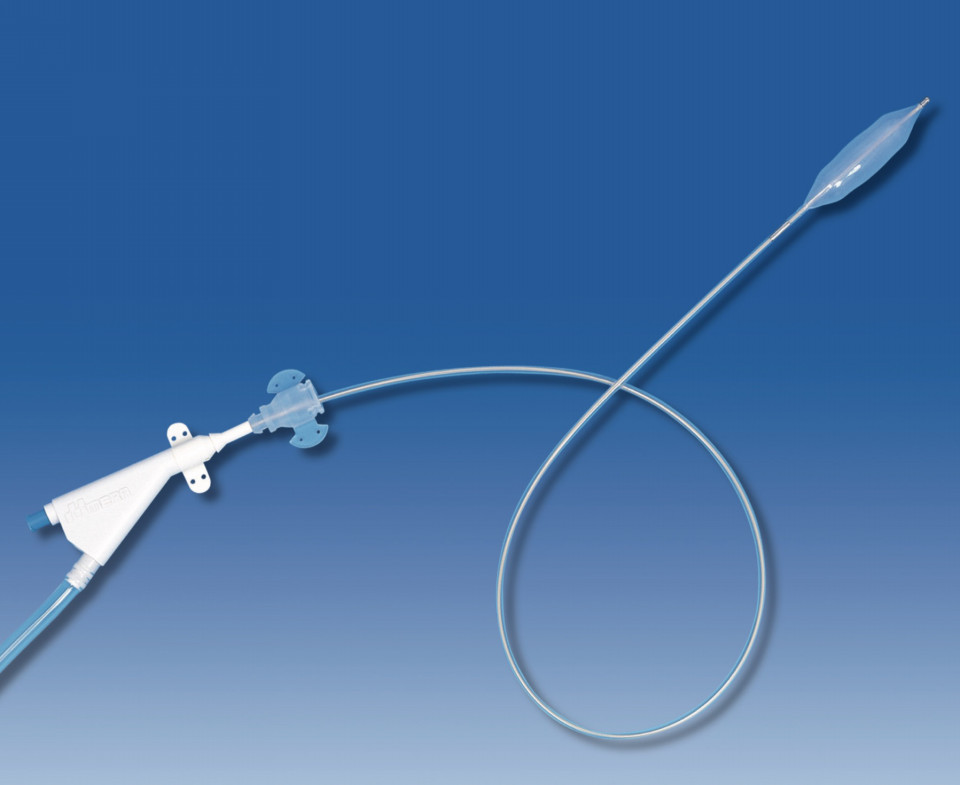

開腹手術にて動脈が3箇所傷あり止血処置